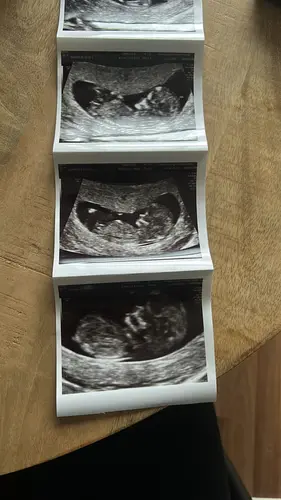

Baby 1, wat zou t worden?

Baby 1 🩵